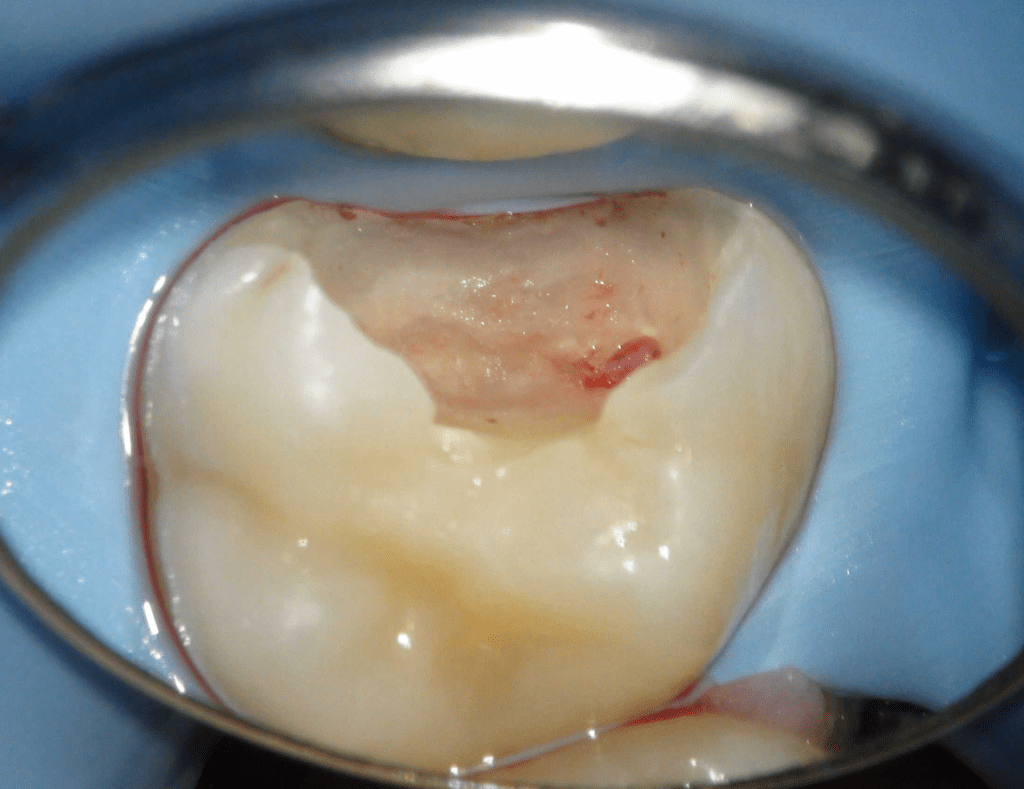

Pulpotomía biodentine + reco preendio